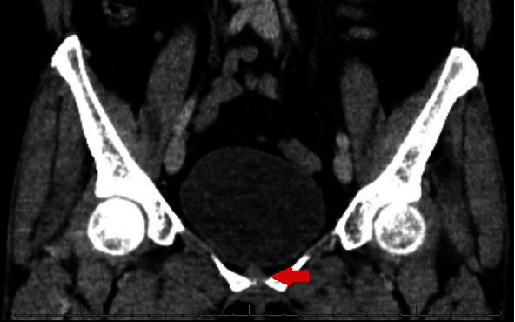

软骨瘤通常发生在骨骼中,在软组织中发现的文献有限。迄今为止,仅有 8 例膀胱软骨瘤的报道,且均为女性。在此,我们描述了一名 54 岁女性的病例,她的膀胱前壁长了一个软骨瘤。在进行造影剂增强计算机断层扫描(CT)时,意外发现右侧膀胱壁上有一个 5 毫米的增强病灶。随后的膀胱镜检查未发现任何异常,尿液分析和尿液细胞学检查也无异常。然而,CT 尿路造影再次证实了恶性肿瘤的怀疑,膀胱镜检查也验证了这一点。患者接受了经尿道膀胱肿瘤切除术,该肿瘤被确认为膀胱软骨瘤。在手术切口中,发现了粘膜下病变,组织病理学评估进一步证实了这一点。经过一年的影像学和尿液细胞学随访,未发现复发。该病例证实了之前的研究结果,并强调该病好发于五至七十岁的女性,预后良好。

Chondroma, commonly observed in the bones, has limited documentation when found in soft tissues. To date, only 8 chondromas in the urinary bladder have been reported, all in females. Here, we describe a 54-year-old female who presented with a chondroma located at the anterior wall of the urinary bladder. An incidental 5 mm enhanced focus was identified on the right bladder wall during a contrast-enhanced computerized tomography (CT). Subsequent cystoscopy did not reveal any abnormalities, and both urinalysis and urine cytology were unremarkable. However, a CT urogram reconfirmed suspicions of malignancy, which a cystoscopy validated. The patient underwent a transurethral resection of the bladder tumor, which was identified as a bladder chondroma. During the surgical incision, a submucosal lesion was found, which was further confirmed with histopathological evaluation. Over a year-long follow-up using imaging and urine cytology, no recurrence was observed. This case reinforces earlier findings and underscores the predilection for females between their 5th and 7th decades with a positive prognosis.